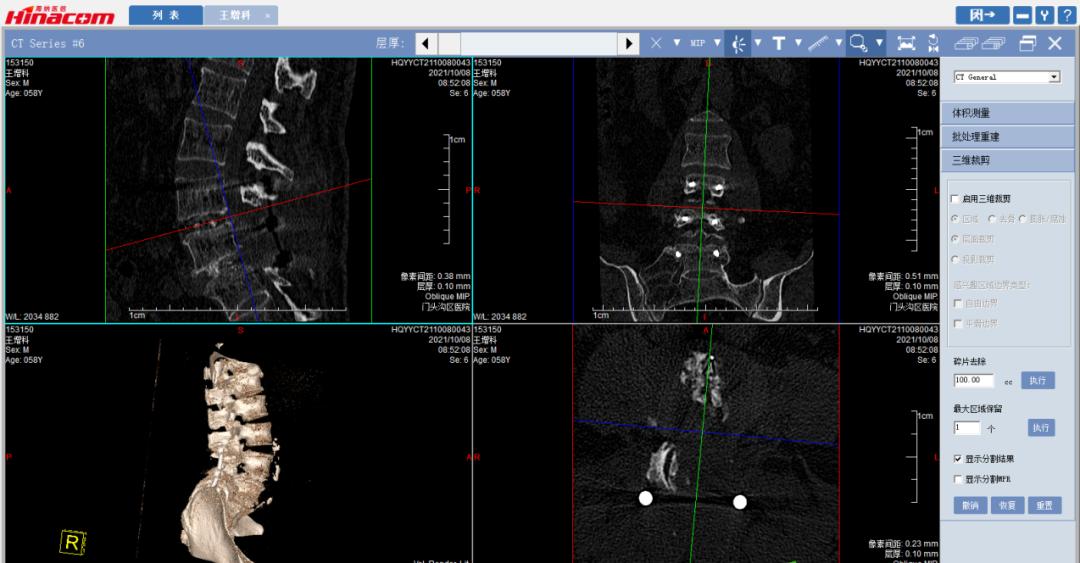

经匡正达主任诊治后,发现患者有先天性腰椎骶化,极易误诊,如果间隙做错了,那后果不堪设想。又考虑到患者要干农活,如果单纯椎管减压,有术后不稳的可能,而且患者长期生理性脊柱侧弯,综合考虑,最终决定为患者实施腰椎管减压的同时,进行椎间植骨融合钉棒内固定术。

手术于2021年9月26日顺利实施。术后,患者十几年来的下肢麻木疼痛和跛行终于消失了! 可以堂堂正正的走路,让王某一下显得年轻了十几岁!